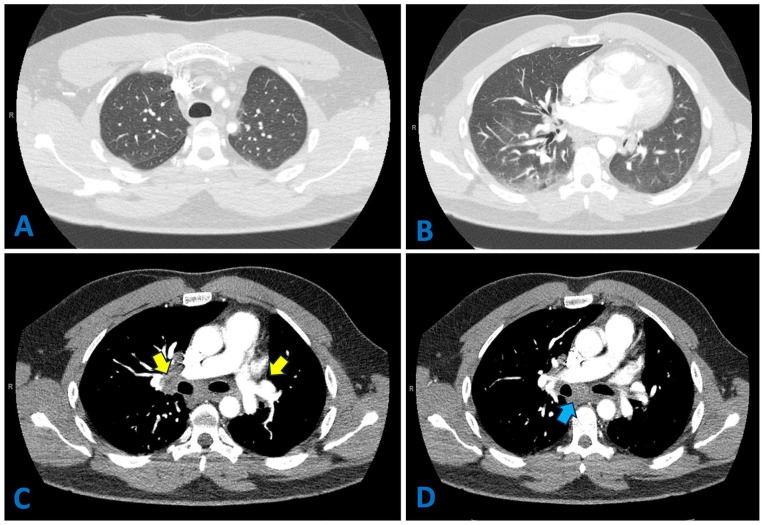

Sarcoidosis is a systemic granulomatous disease that predominantly affects the lungs. However, its presentation as a giant pulmonary bulla is exceptionally rare. Its association with COVID-19 has raised new concerns regarding disease exacerbation and misdiagnosis. We report a case of a 38-year-old man who developed a large left lower lobe bulla in the context of recent COVID-19 infection. Initial misinterpretation of the bulla as loculated pneumothorax nearly led to an unnecessary chest tube placement. A subsequent thoracotomy with lobectomy revealed nonnecrotizing granulomas, confirming sarcoidosis. The patient showed spontaneous remission without requiring treatment. This case highlights the importance of multidisciplinary discussions in atypical lung presentations to prevent mismanagement.